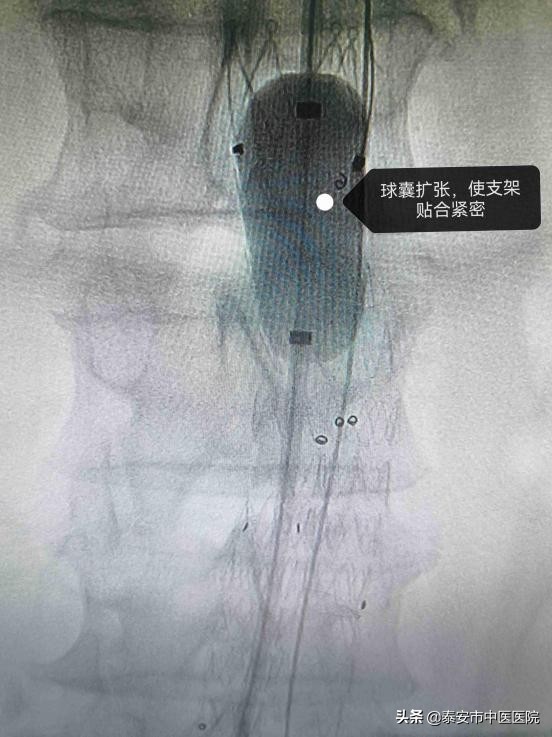

球囊扩张,使支架贴合紧密

支架精准释放,腹主动脉瘤被隔绝在支架外,出血风险解除